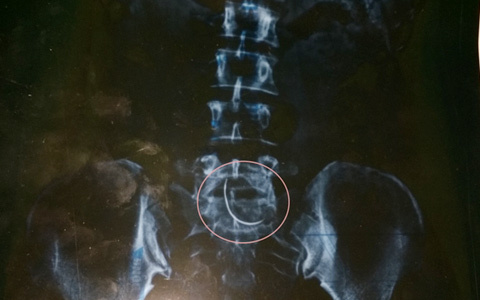

Hình ảnh chiếc kim khâu cong vút từ phim chụp X-quang của chị Hòa.

Thế nhưng, để chắc chắn, ngày 5/11, anh Tiến lại đưa vợ ra BVĐK Cửa Đông (TP Vinh, Nghệ An) kiểm tra. Nhận kết quả phim chụp từ tay bác sĩ, anh Tiến và chị Hòa không tin vào mắt mình, hình ảnh một chiếc kim cong vút nằm ở vùng bụng chị Hòa.

"Tôi thực sự không biết vì sao chiếc kim khâu lại nằm trong bụng mình. Hơn nữa nó lại nằm ở chỗ vết thương mà trước đây các bác sĩ tại BVĐK Can Lộc tiến hành mổ. Nhìn phim chụp mà tôi sởn gai ốc", chị Nguyễn Thị Hòa nhớ lại.

"Chiếc kim đó cong cong như lưỡi câu cá, có độ dài chừng 3- 5 cm. Nghĩ tới đó thôi là cả người tôi ớn lạnh", chị Hòa rùng mình nói.